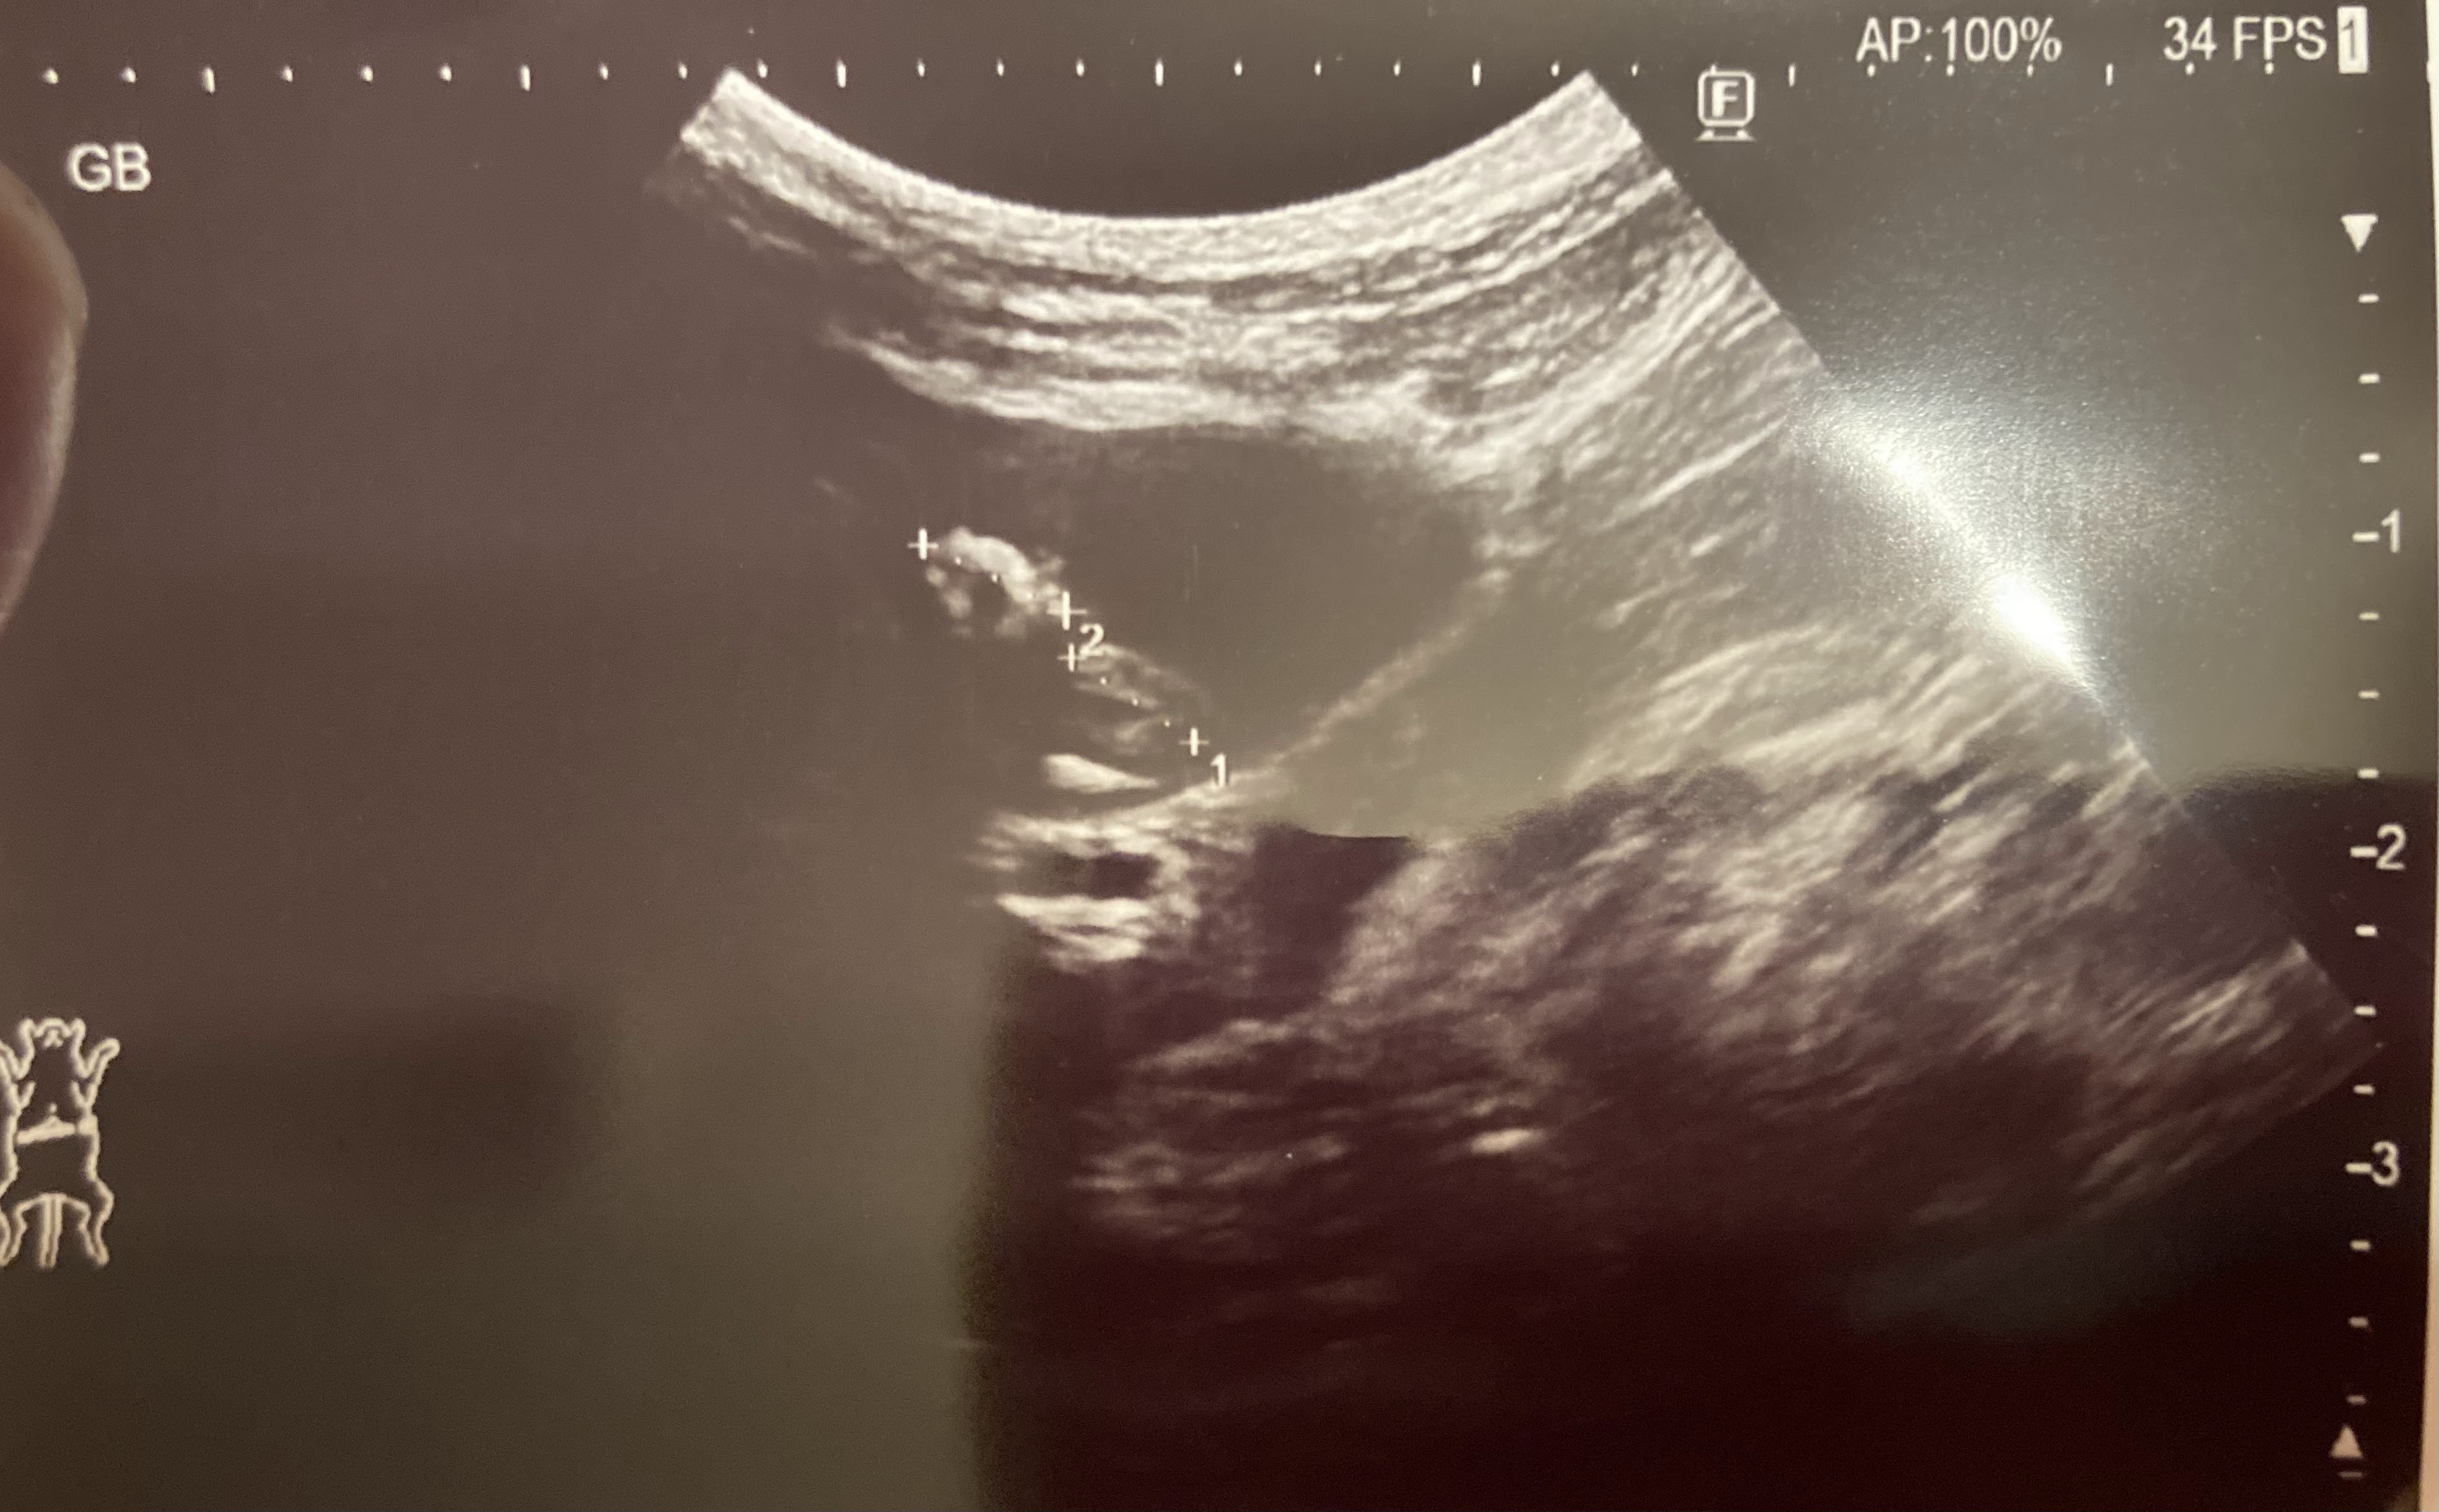

エコーでも、レントゲンでも胆石はありますが、周囲はそれほど汚くないそうです。

ただ、膀胱の中にちょっと漂うものが見えると言うことで、